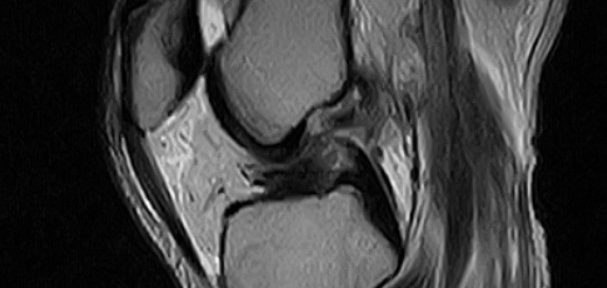

スロバキアからハンガリーに戻り、整形外科を受診した。関節穿刺によって関節液を抜いた。1月9日にMRI撮影を行い、以下の診断を得た。

右膝前十字靭帯断裂(断裂した断端が翻転(Iharaの分類Ⅲ))

右膝内側側副靭帯損傷

右膝外側側副靭帯損傷

2月17日、再度MRI撮影を行った。膝完全伸展位での撮影であった。今回のMRI画像では、自然治癒は確認できなかった。むしろ、断端同士の距離は広がり悪化していた。脛骨側の断端は、翻転位のまま改善されていなかった。